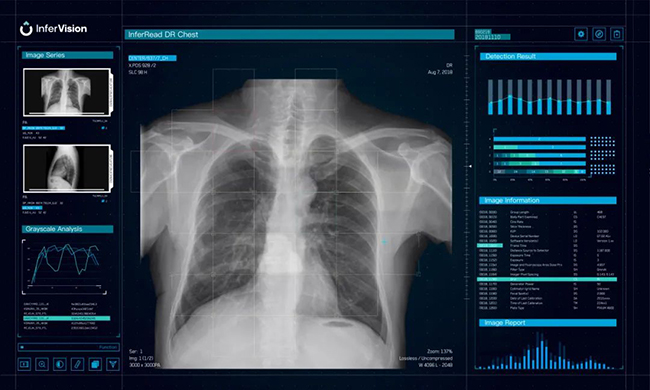

▲推想DR产品概念图

▲便携式x光机+AI技术的肺结核移动筛查车,能够在大规模范围内,快速发现患者,第一时间进行治疗,从而从根本上减少结核病的发病率